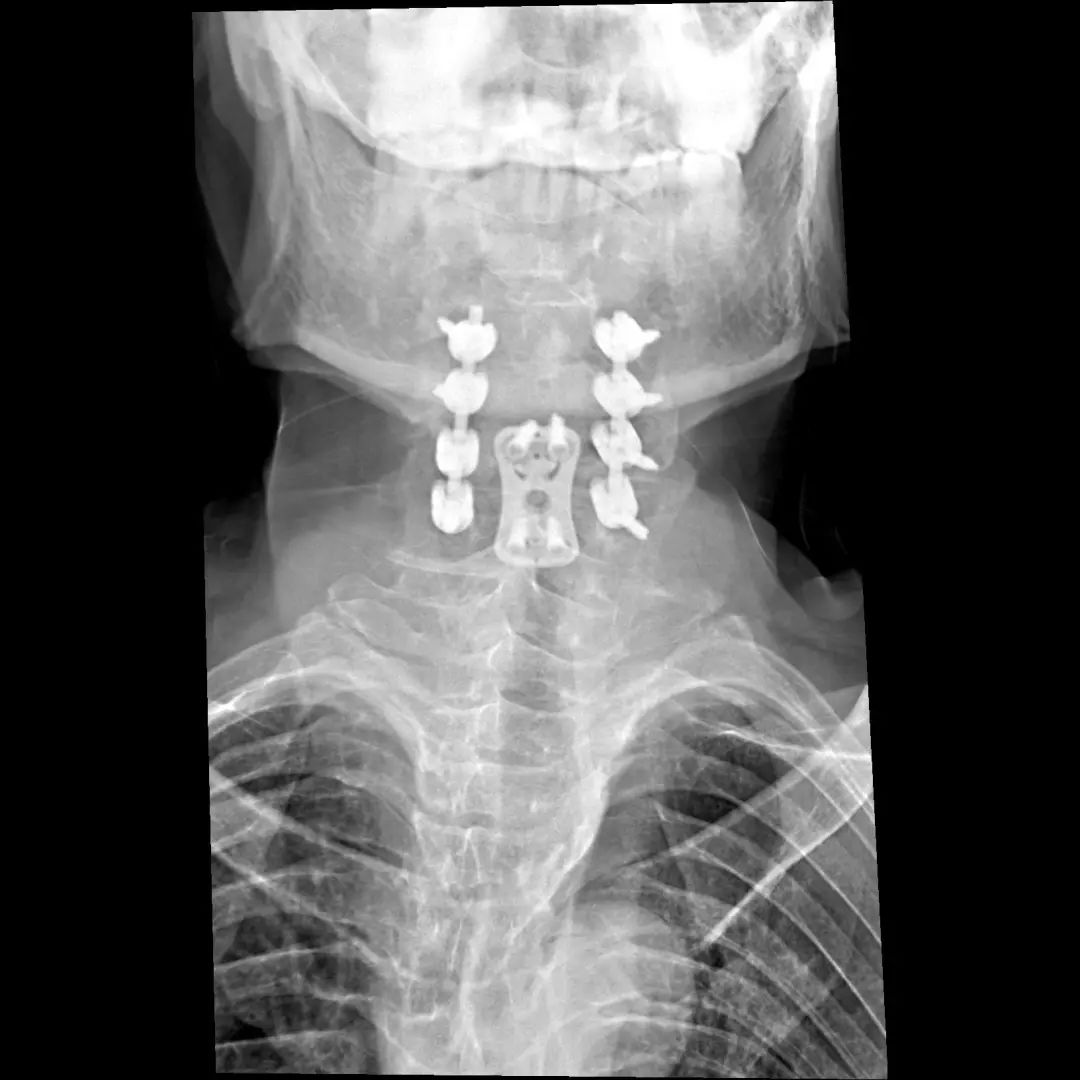

经过全程监护和系统治疗,患者术后恢复良好,骨折解剖复位,复查X线及CT显示固定位置佳,术后3天下地行走,术后4天即出院回家休养。

枕颈融合术

颈椎骨折脱位前后联合减压固定术